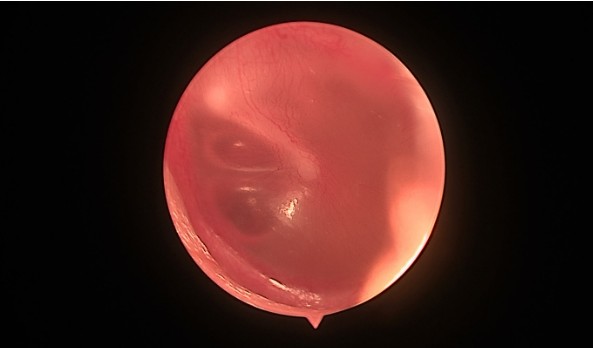

Отоскопия: ушные раковины обычной формы, наружные слуховые проходы широкие, барабанные перепонки втянуты, серо-розового цвета, визуализируется экссудат (представлено на фото).